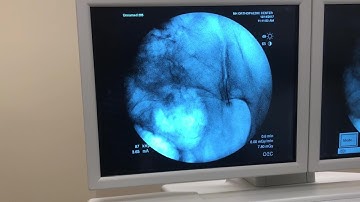

C-Arm Guided Sacroiliac Joint Injection: Step-by-Step Procedure